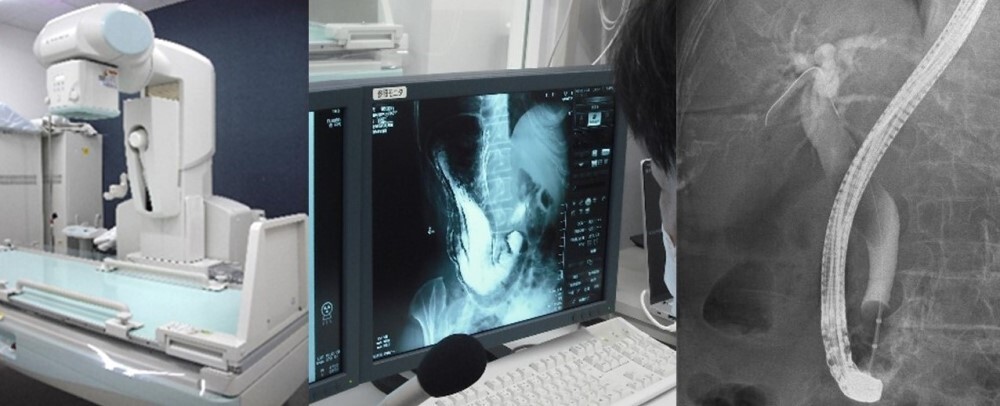

X線TV透視撮影検査

X線TV透視撮影検査とは、通常のレントゲン写真と異なり、X線を連続して照射しながら行う検査です。食道・胃・十二指腸の病変をチェックするためのバリウム検査などがあります。

写真:X線TV透視撮影装置